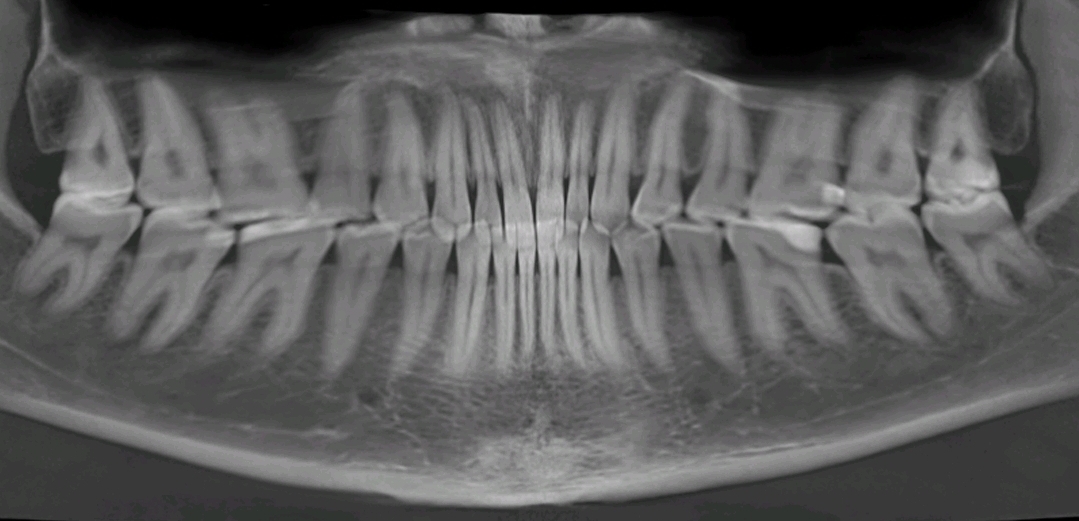

Всем доброго дня.

Имеется постоянная ноющая боль снизу справа, где-то в районе 6-7-8.

Реакции на холодное, горячее не замечал.

Была подобная проблема год назад, переделали пломбу на 6. Проблема ушла сама собой, но через месяца полтора. Сейчас вернулась и по ощущениям сильнее.

Также между 6 и 7 есть место куда постоянно забивается пища.

Подскажите варианты, пожалуйста, очень не хочется депульпировать зуб.

Снимки майские.

Удалить восьмерку, заменить пломбу в шестерке.

Как минимум неплотный контактный пункт - из-за этого у Вас забивается пища между зубами.